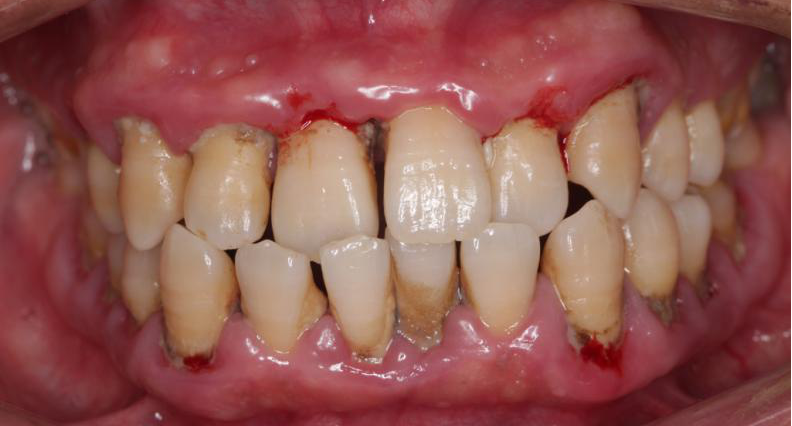

长沙60岁的赵大爷因为牙齿问题连日来无法吃东西,到捷克论坛 马王堆院区口腔二科就诊,赵大爷告诉医生,自己因为牙齿原因苦不堪言,人也消瘦了不少。医生经过检查诊断赵大爷是患上了牙周炎,他的口腔内不仅有大量的牙结石堆积且牙龈红肿出血,还有严重的口臭,多颗牙齿摇摇欲坠,最终,只能拔除这些松动的牙齿,等待3个月后进行镶牙治疗。

很多人觉得奇怪,为什么没觉得痛,就会出现牙龈萎缩、红肿出血,甚至牙齿松动、脱落,张特主任指出,这就要认识什么是牙周炎。每个人口腔中都有牙菌斑,其粘附在牙齿表面或口腔其他软组织上。早期可以通过高效的刷牙去除,如果刷牙不彻底,牙菌斑会大量堆积形成硬化的牙结石,一旦牙结石达到相当程度,将不可避免刺激牙龈发炎,刷牙出血,就是单纯的依靠刷牙或口服消炎药已经无法去除病因。当炎症持续进展,将出现牙周袋、牙槽骨吸收、牙齿松动和口臭,发展为牙周炎。

张特介绍,之所以很多患者一开始没有感觉,是因为牙周炎是一个进展相对缓慢的疾病,早期的症状一般为牙龈红肿、偶尔刷牙及咬物出血、牙龈边缘出现刷牙不能去除的黄色牙结石、牙缝增宽、牙龈萎缩、牙齿酸痛敏感等,这些小毛病无关痛痒,所以容易被忽视。当牙周炎继续进展到严重期,患者的牙齿陆续出现松动,渐渐地咬物无力到最后无法进食,这时候已经为时已晚,有时甚至无力回天,只能拔除,接受镶牙或者种植牙,给患者带来经济负担,影响正常生活。